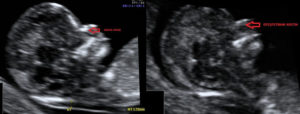

В качестве примера приведем несколько примеров: 1. Ниже на УЗИ мы видим нормальную носовую кость. Можно различить 3 четкие линии.

2. Гипоплазия носовой кости. УЗИ сделано на 12 неделе беременности. Длина — 1,4 мм (ниже границы нормы).